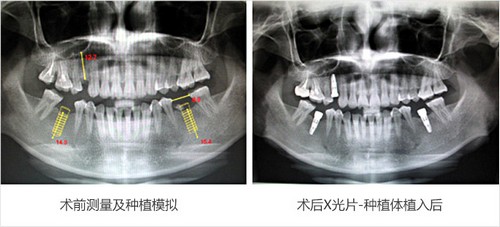

所以,缺牙较 好在三个月内种上,此时牙槽骨条件较好,进行种植修复有利于骨结合。而较 佳的时期,是即拔、即种,此时口腔内所有数值是较 佳的,这个时候种牙,省心、省时、省钱。

即拔即种即用:种植牙体与牙槽骨高度融合,牙槽骨条件好的患者当天即可戴牙冠和进食,快速恢复真牙咀嚼功能。